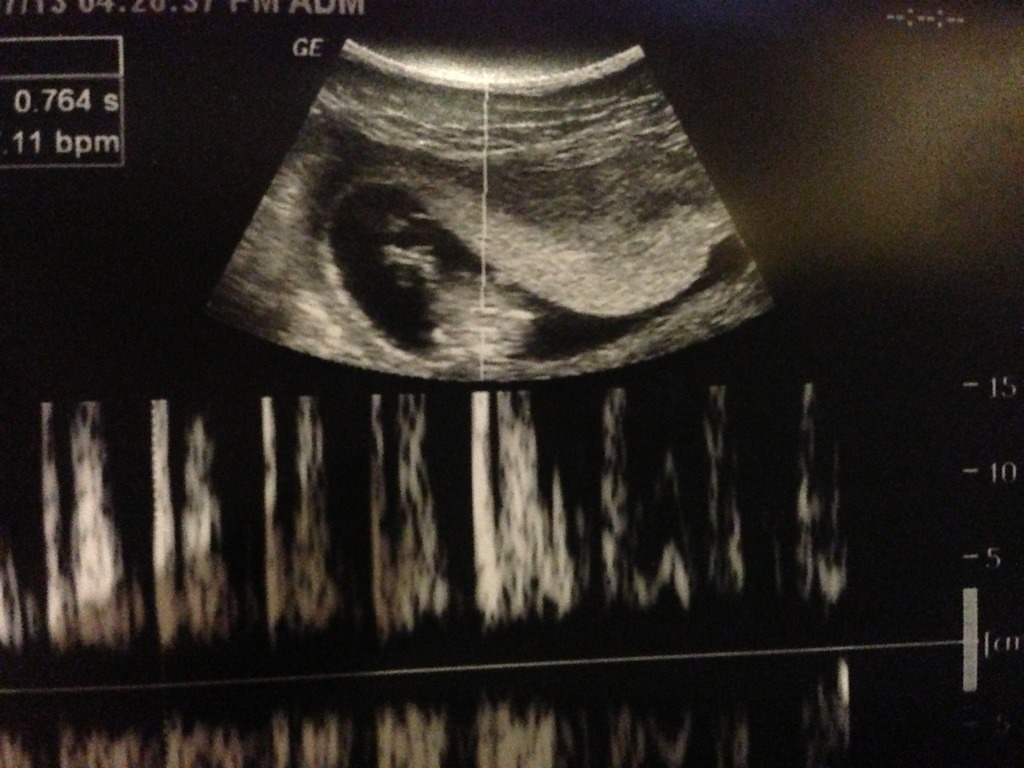

Well I had my 11 week appointment (11 weeks on the dot) with my fantastic obstetrician today and told him we will find out gender ASAP. He gave me a scan and looked down there, while commenting that the NT scan place at 12 weeks was having amazing success determining gender and I could probably find out then. He lined up a potty shot angle and immediately when he and I saw the screen we looked at eachother, I said "I saw that" and he laughed, and asked what I thought that was, I said "it's a boy isn't it?" And he said "I'm almost certain, it's early, but I don't see that turning into a vagina" It was literally a penis length bit sticking out between the legs. I'm 99% sure it wasn't cord because of the way it ended and where it was.

I didn't ask for a nub shot because I had no doubt. But now at home I'm desperate to convince myself it could be wrong! I thought at 11 weeks it couldn't even BE a penis but it seriously looked like one. I know all about nub theory and how potty shots at 11 weeks can be wrong, but did anyone see a big long thing between the legs and seriously have it turn out to be a girl?